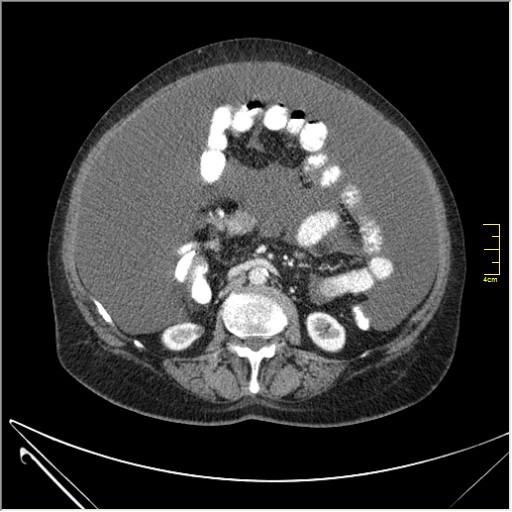

Женщина 72 года. Поступила с жалобами на вздутие живота. После осмотра хирургом, была сразу направлена на КТ брюшной полости.

Итак, асцит с объёмным образованием таза. В данном случае можно быть более конкретным, у пациентки неоплазия правого яичника с региональной лимфаденопатией (увидели?) и выраженным асцитом, характерным именно для злокачественных опухолей яичников. Пациентка оперирована ( операция Вертгейма); диагноз верифицирован: аденокарцинома правого яичника (серозная). Направлена к онкологу для дальнейшего лечения.